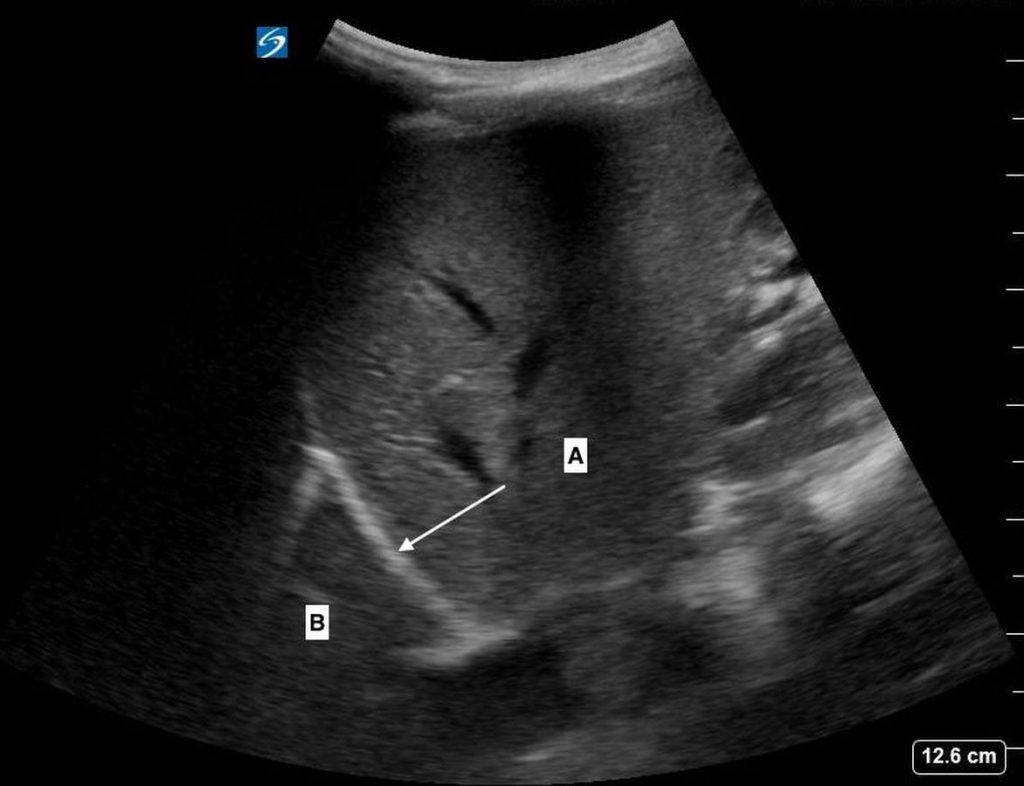

Thoracic Limited Bedside Thoracic Ultrasound A. Clip of bilateral sliding lung https://vcuultrasound.com/wp-content/uploads/2020/07/3e626-video-4.3-lung-sliding.mp4 B. Clip of bilateral upper and lower lung looking for B-Lines (4 separate clips) https://vcuultrasound.com/wp-content/uploads/2020/07/6045d-video-4.1-b-lines.mp4 C. Clip of bilateral costophrenic angles A) Costrophrenic angle B) Lung Share this: Share on X (Opens in new window) X Share on Facebook (Opens in new window) Facebook Like Loading...